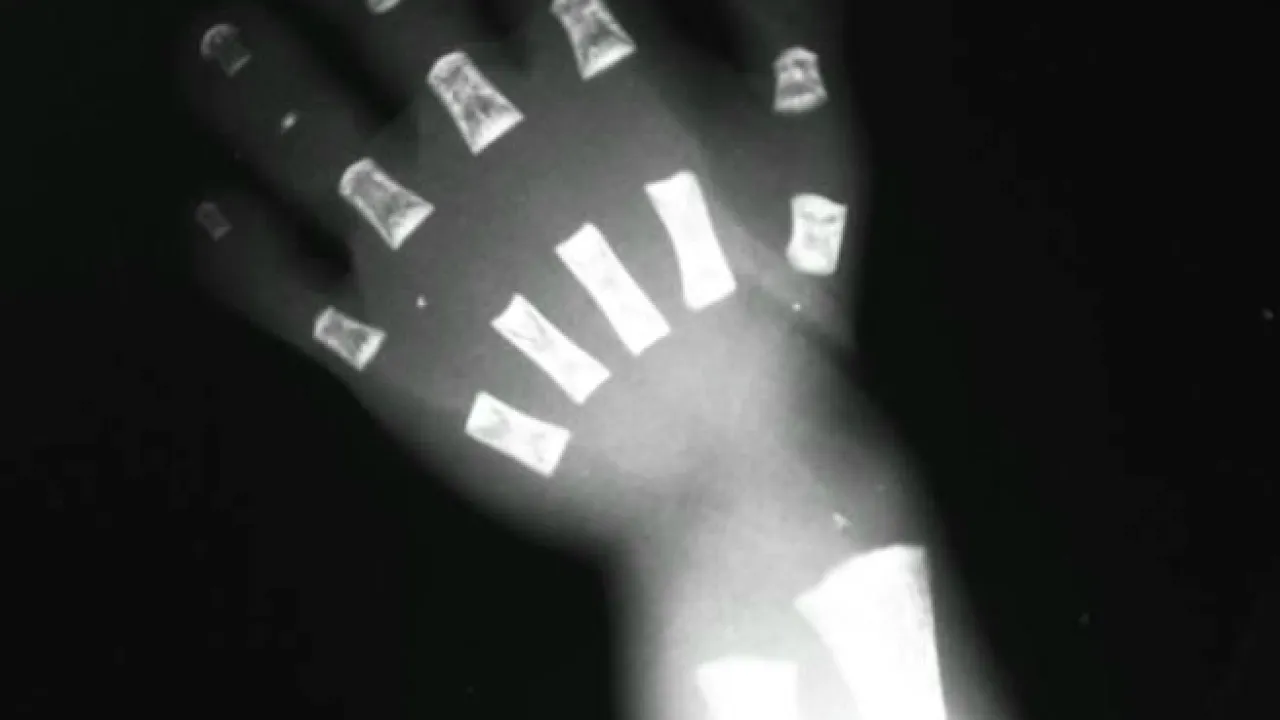

Bones, Robinow Syndrome